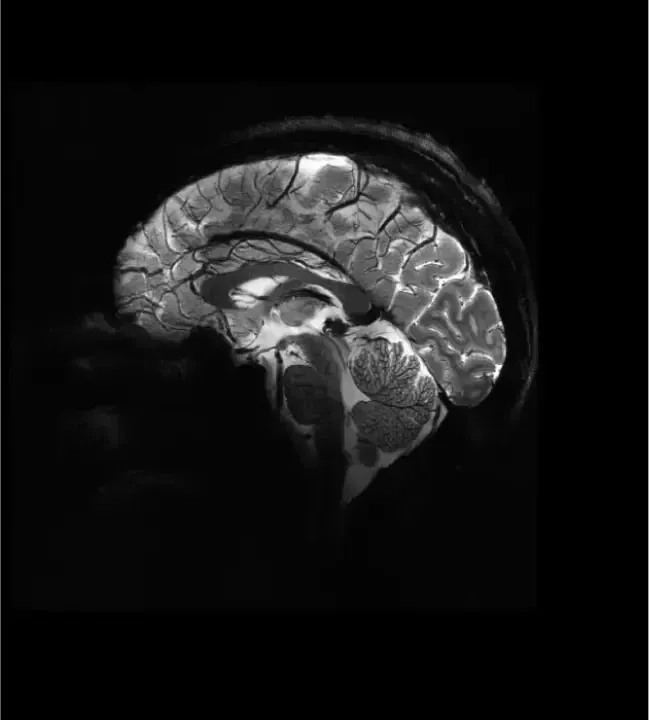

Procedure: MRI of the brain was performed at tesla

Findings:

Ventricles: Normal in size and configuration without evidence of hydrocephalus.

Bones: Calvarium and skull base show normal bone marrow signal, no destructive lesions

IMPRESSION: No acute intracranial abnormality.